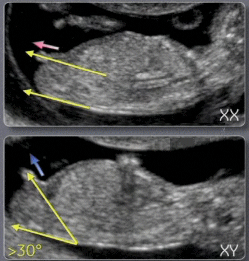

Sur cette photo tu vois bien la différence